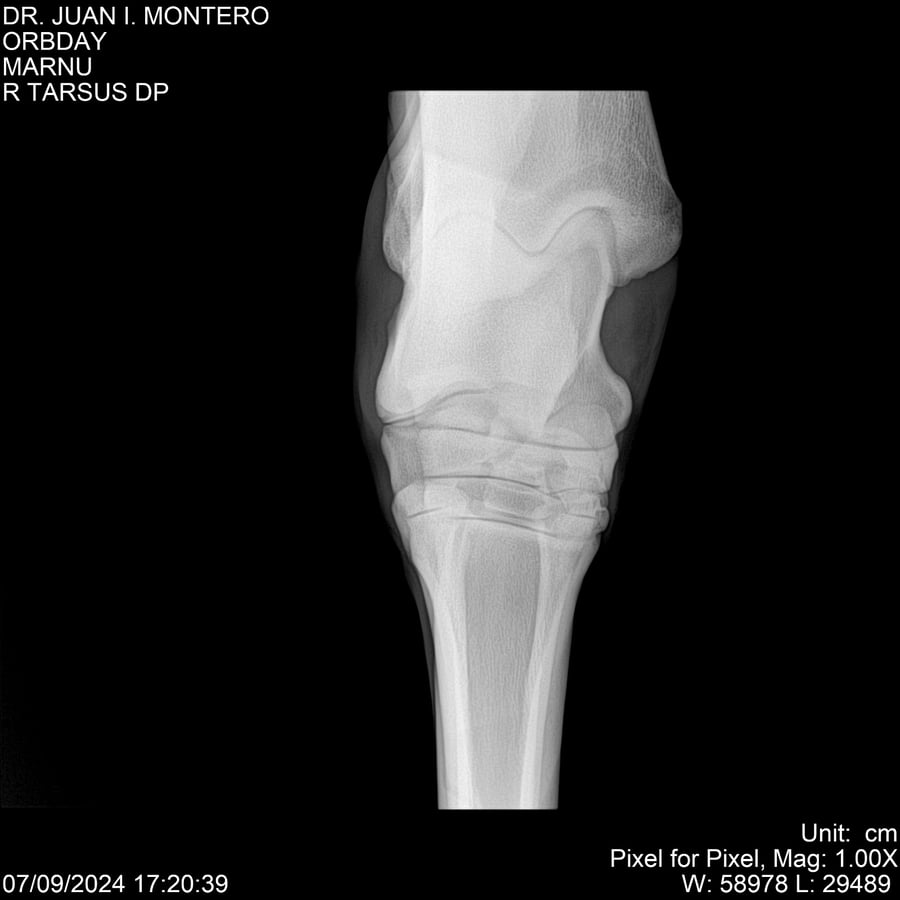

• Empresa: Abelenda N. R., Walter Hugo